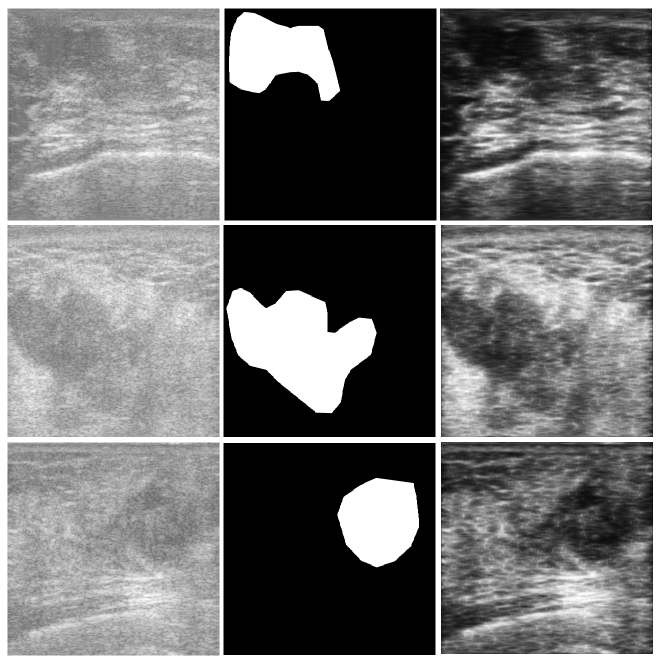

As evident from the relatively low contrast images shown in Fig. 3, any segmentation technique will have difficulty to extract the tumours as marked by the expert. This was verified by experimenting using several methods such as thresholding, active contours, and watershed segmentation. As the ultimate goal is to characterize the tumour for treatment prediction, we can aim to get an ROI segmented that roughly sketches the tumour region instead of attempting to extract the precise tumour contour. Hence, we propose to use a novel approach, namely barcode-guided ROI segmentation, which aims at finding a bounding box around the tumour instead of actual tumour contour.

where was a proper membership function, and had darkening effect on the image. To suppress the speckle noise present in ultrasound images, sticks filter [23] was used. Fig. 3 shows some sample images with their corresponding ground-truth, and preprocessed versions.

4 Leave-One-Out Validation